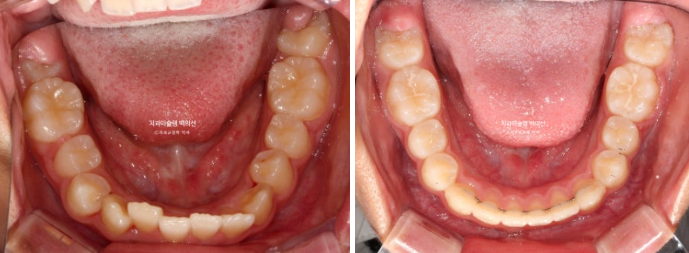

24.02~25.07

24년 1월 교정치료를 위해 온 만 10세 어린이입니다.

공간부족으로 인한 덧니가 심해 반대교합이 있습니다.

악궁확장을 통한 덧니 배열을 목표로 인비절라인 퍼스트 교정치료를 권유드렸습니다.

24년 2월부터 9월까지 첫세트의 19개 장치를 모두 낀 후 모습입니다.

중심선은 개선되었으나 약간의 불일치가 남아있으며 반대교합과 덧니는 모두 개선되었습니다.

어긋난 중심선이 맞아졌으며 기울어진 앞니 치축도 좋아졌습니다.

앞니가 깊게 물리는 과개교합도 좋아졌습니다.